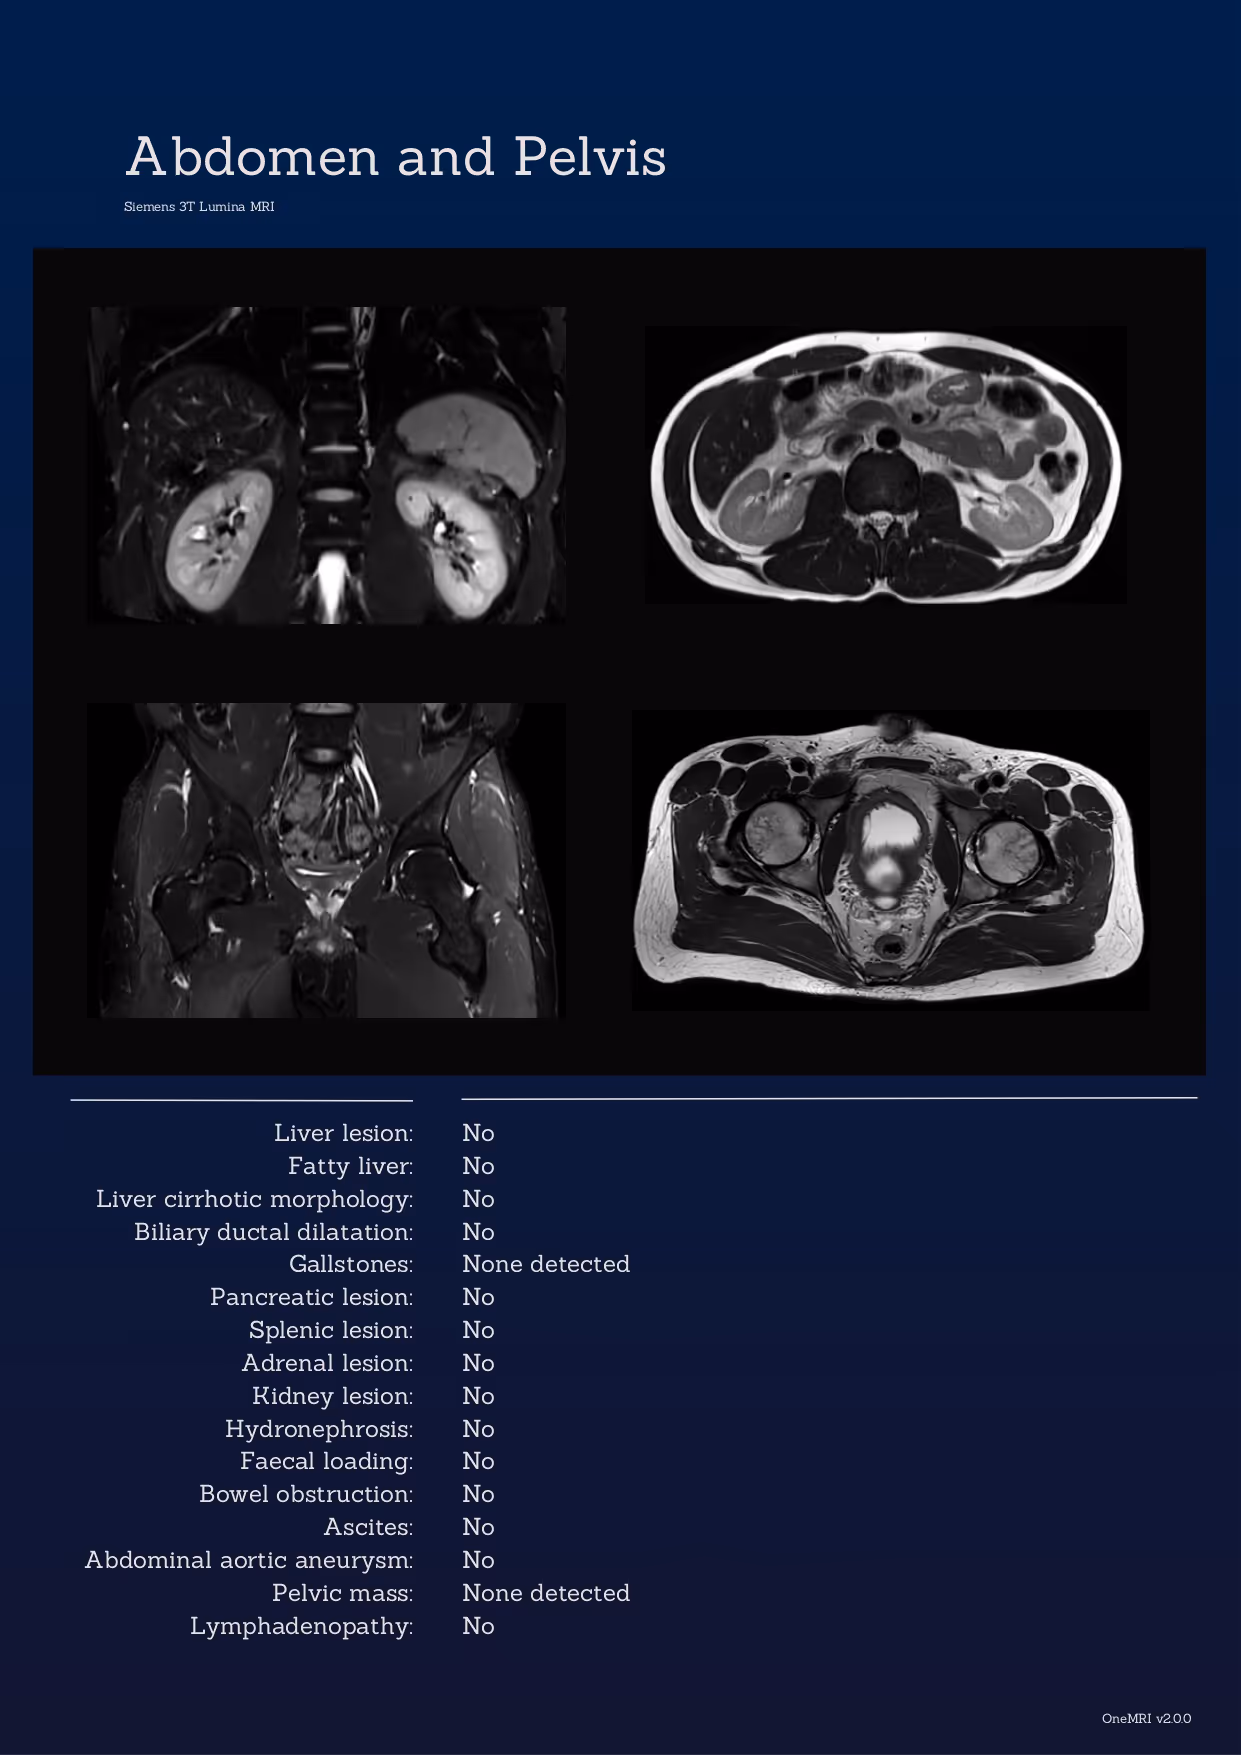

Your report is more than a summary. It is a complete, visual overview of your health. Each scan includes annotated images, clear explanations of any findings, and a summary that highlights areas for follow-up.

Tap images below to explore examples.